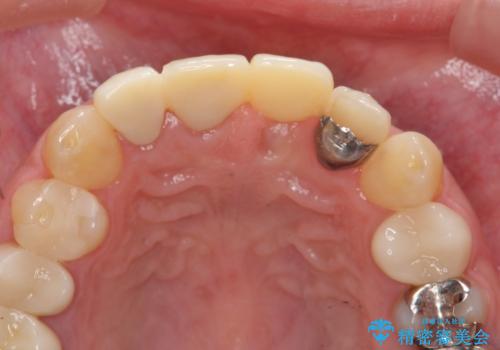

左側の前歯には他院で埋入されたポジションの悪いインプラント補綴により歯冠長の長いクラウンが装着されており、感染による排膿も認められこのまま審美性を改善するのは難しい状態です。

感染したインプラントからは排膿が間欠的に認められ、掻爬・除去が検討されうるような状況でした。

より審美的な改善を強く求められたため、インプラントを除去し可及的に欠損部顎堤を増大したのちブリッジによる審美改善を行いました。